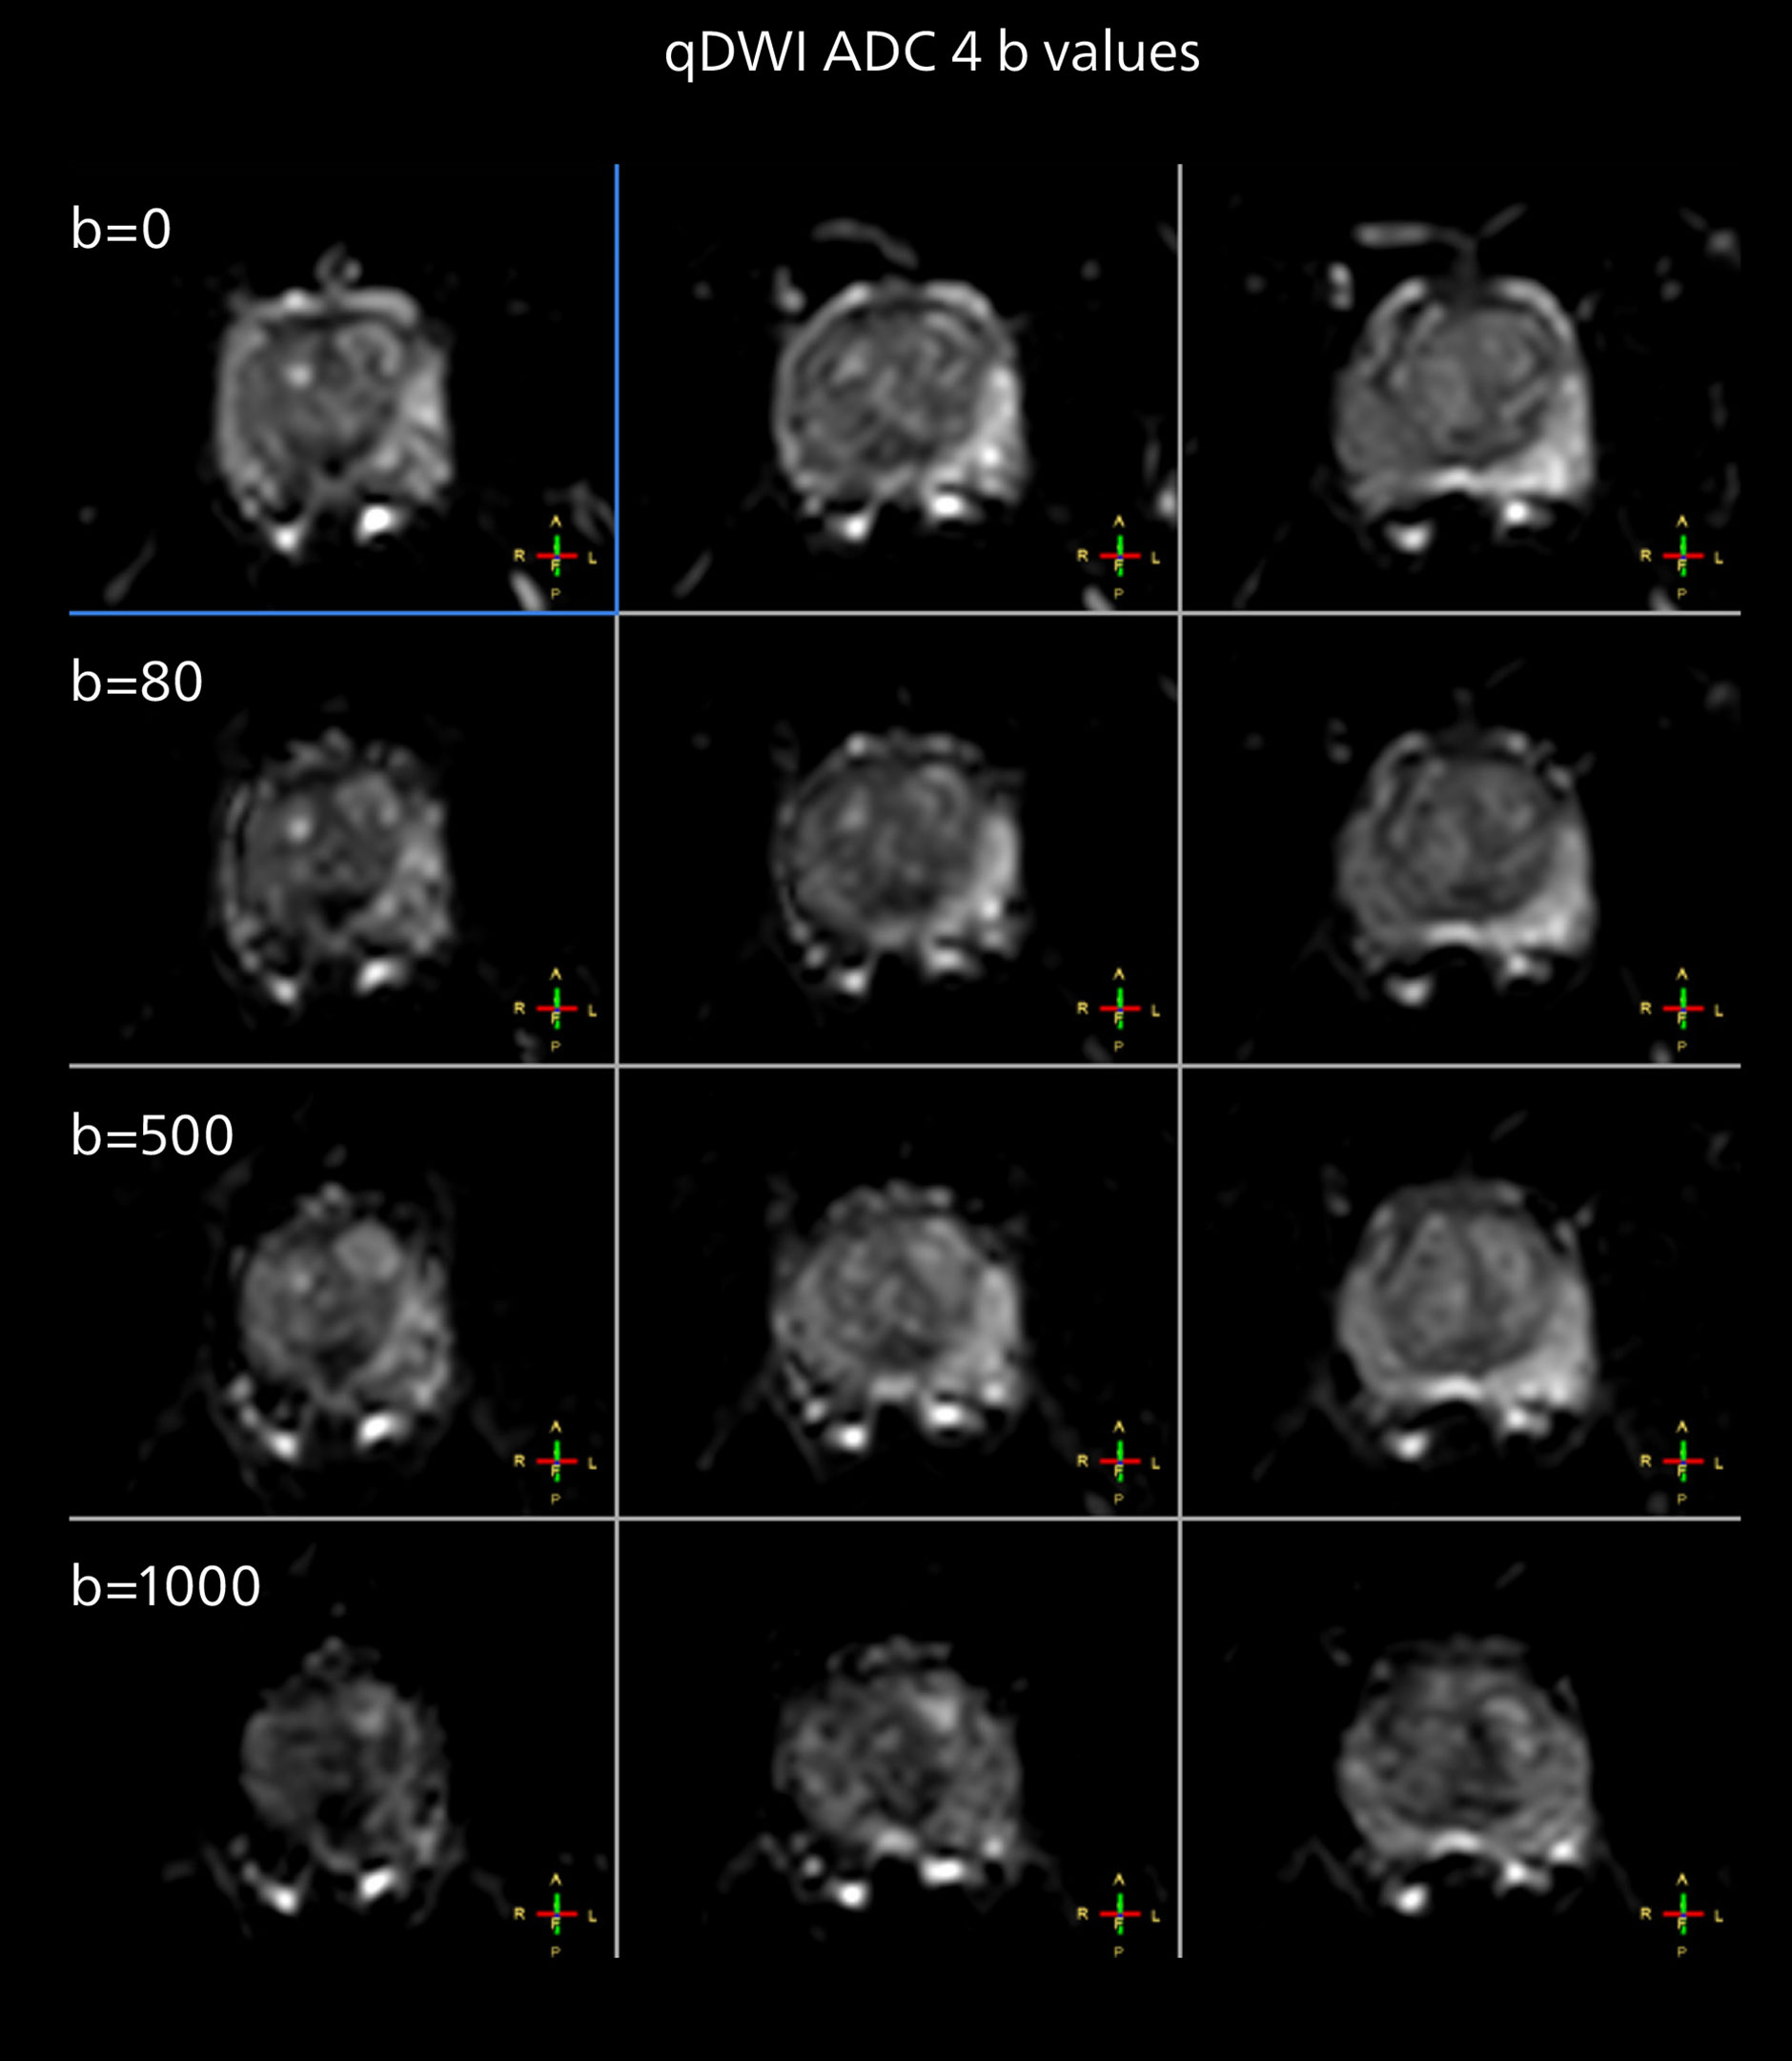

Diffusion weighted imaging of prostate

The examples on the left show the regular clinical diffusion protocol with four b-values up to b1000 s/mm². On the right, the T2W image shows a hypointense lesion that has low ADC and is clearly visible in b1400 and b2000 diffusion images, suggesting malignancy.